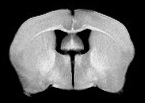

La Resonancia Magnética de Imagen (RMI o IRM en inglés), también conocida como Tomografía por Resonancia Magnética (TRM) o Resonancia Magnética Nuclear de Imagen nuclear (RMNI o NMRI en inglés) es una técnica no invasiva que utiliza el fenómeno de la resonancia magnética para obtener información sobre la estructura y composición del cuerpo a analizar. La información es después procesada transformada en imágenes.

Se utiliza principalmente en medicina para observar alteraciones en los tejidos y detectar cáncer y otras patologías.

MRI Clínico de 3T: Achieva 3,0 T TX de Philips.